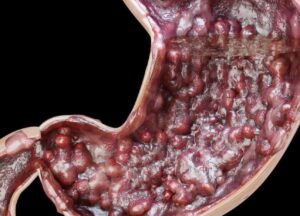

El cáncer de estómago, también conocido como cáncer gástrico, es una enfermedad en la que las células malignas se forman en el revestimiento del estómago. Aunque sus causas exactas no siempre son claras, existen diversos factores de riesgo que pueden contribuir a su desarrollo, como la infección por Helicobacter pylori, el consumo excesivo de alimentos procesados o ahumados, el tabaquismo, el alcoholismo y antecedentes familiares de la enfermedad.

El diagnóstico del cáncer de estómago se realiza mediante diversas pruebas médicas, como la endoscopía digestiva alta, en la que se introduce un tubo con una cámara a través del esófago hasta el estómago para observar posibles anomalías. También se pueden realizar biopsias, análisis de sangre, tomografías computarizadas (TC) y resonancias magnéticas para obtener una visión más detallada del estado del estómago y la posible propagación del cáncer a otros órganos.